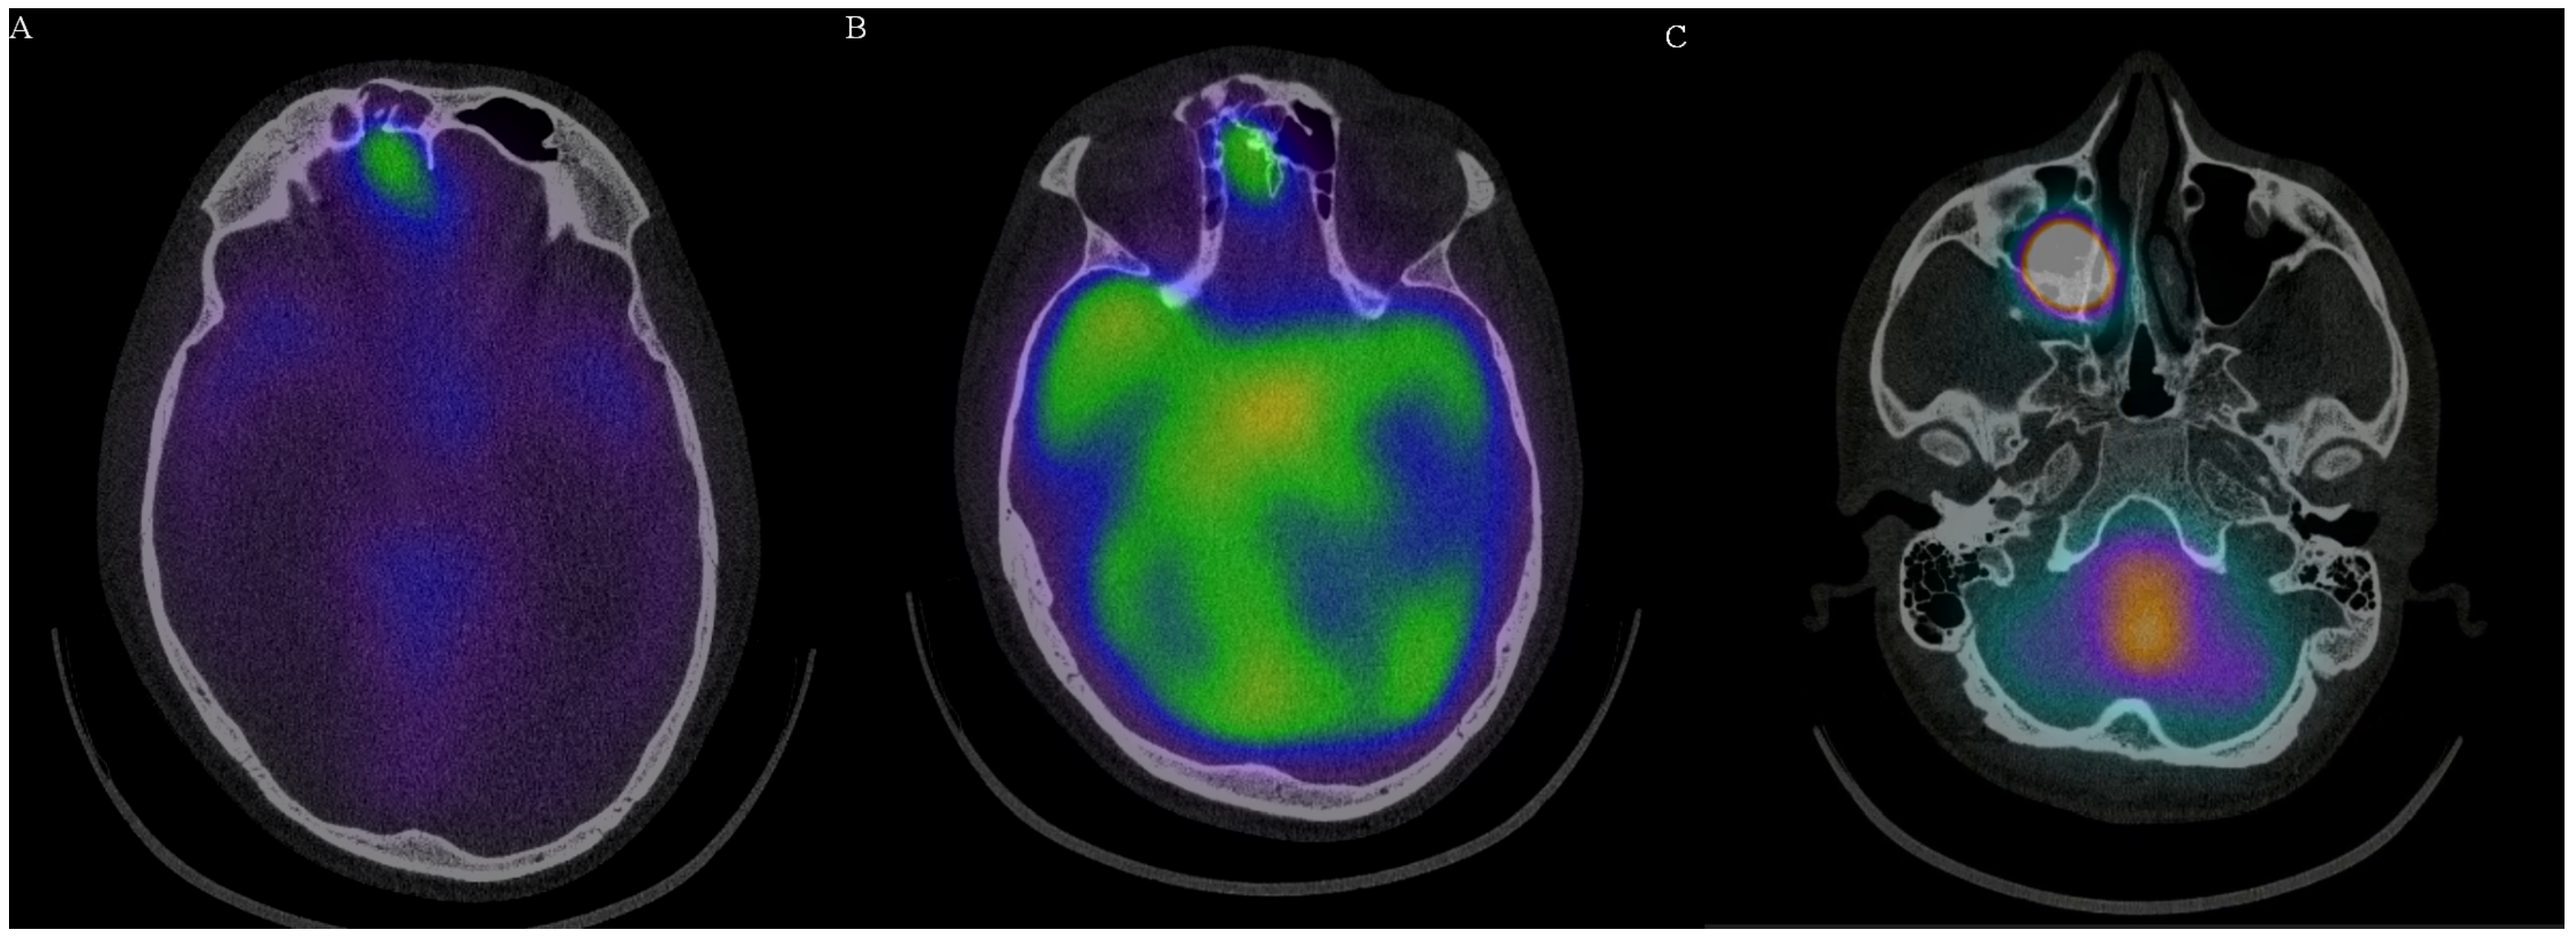

Diagnostic Value of Radioisotope Cisternography Using 111In-DTPA in a Patient with Rhinorrhea and Purulent Meningitis

2. Case Report